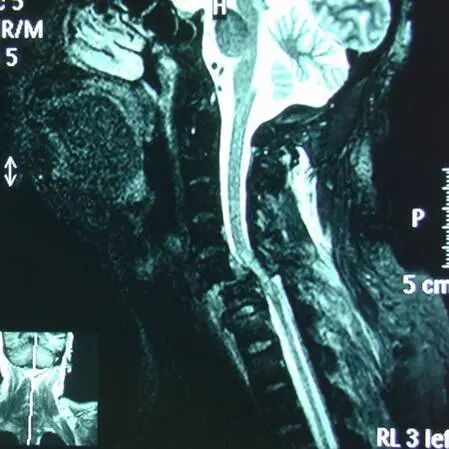

脊髓损伤影像学诊断

脊髓损伤平面诊断